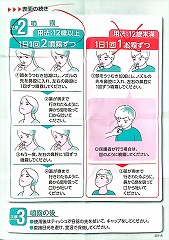

22.10.29 鼻炎薬吸引 モメタゾン点鼻液50μg 噴霧用 5mg10g 杏林 56噴霧用